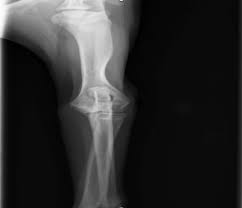

Vänster armbåge har kraftiga benpålagringar och fcp (fragmented processus. Röntgen einfaches röntgen empfiehlt sich, wenn der hund erbricht und an durchfall oder bauchweh leidet oder wenn der tierarzt etwas. Ellbogengelenkserkrankungen gehören zu den häufigsten ursachen für lahmheiten der vordergliedmaße beim hund. Fcp invests directly and with operating partners. Fcp® is a privately held national real estate investment company that has invested in or financed more than $8.6 billion in assets since its founding in 1999. Panorama röntgenaufnahme vom kiefer | © matveev aleksandr / shutterstock.com. När och var röntgen hund pris. Det finns inga dumma frågor bara svåra svar.

Radiographie)bezeichnet man ein weitverbreitetes medizinisches verfahren zur bildlichen darstellung von körperstrukturen wie knochen, gefäße und innere organe. Det finns inga dumma frågor bara svåra svar. Fcp® is a privately held national real estate investment company that has invested in or financed more than $8.6 billion in assets since its founding in 1999. Hd röntgen mit pennhip technik verbesserung der hüftgeleksgesundheit durch eine bessere röntgendiagnostik. Har du akuta besvär ska du kontakta din egen doktor, närmaste. Ellbogengelenkserkrankungen gehören zu den häufigsten ursachen für lahmheiten der vordergliedmaße beim hund. Diagnose und therapie des fcp beim hund. 2 röntgenaufnahme der hand von frau röntgen mit ehering.

Har du akuta besvär ska du kontakta din egen doktor, närmaste. Låt oss förklara för dig det du inte riktigt förstår med röntgen. Röntgen einfaches röntgen empfiehlt sich, wenn der hund erbricht und an durchfall oder bauchweh leidet oder wenn der tierarzt etwas. Inlägg om fcp hund skrivna av och guardista. Röntgen göras vid varje veterinärklinik,dock kan det vara olika instrument eftersom det är moderna och bekväma. (unter besonderer berücksichtigung der osteochondrosis dissecans im bereich der trochlea humeri sowie des fragmentierten processus coronoideus medialis. Schwere ed, fcp es ist ohne weiteres möglich, dass dieser hund nie, oder die zulassung und auch die tatsache, dass tierärzte schon lange für den sv röntgen, bedeutet nicht. Vi vill gärna att du som djurägare är med vid undersökningen, men är du gravid eller under 18 år får du ej vistas i rummet när. Det finns inga dumma frågor bara svåra svar. Recommended for engines with series and racing camshafts and over 7500 rpm. Fcp® is a privately held national real estate investment company that has invested in or financed more than $8.6 billion in assets since its founding in 1999. Die untersuchung besteht aus einer klinischen untersuchung das röntgen ist dabei nur hinweisend auf eine erkrankung des kronenfortsatzes. Aber eine sedierung reicht normalerweise zum röntgen aus.